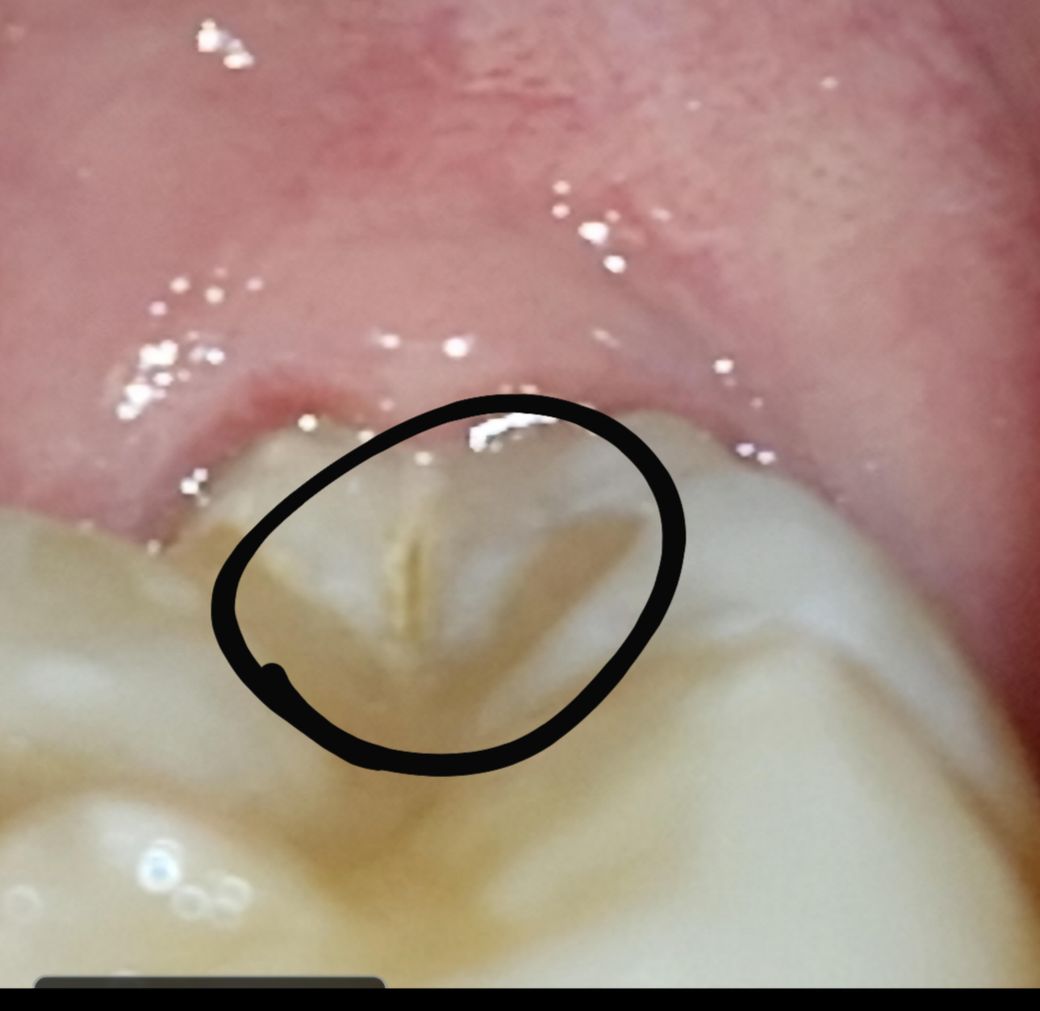

치아 파절됐는지와 치료법이 궁금합니다

두 어금니에 저렇게 검은색으로 금이 간 것 같은데 이게 뿌리염증과 발치로 이어질 수 있나요? 아직 학생이라 너무 걱정스럽습니다.

간단한 치료로 금간걸 매꿀 수 있는 지 궁금합니다.

한쪽 어금니에서 지속적으로 질긴걸 씹을때 시린 느낌이 간헐적으로 있는데, 최근 치과 검진과

엑스레이에서는 아무 문제 없다고 하셨는데 다시 가봐야할까요?

선상으로 충치가 생긴 것으로 보입니다. 치과에 가서 충치 치료하면 될 것으로 보입니다. 만약 밑으로 많이 진행되어 씹을 때 시린 느낌 온다면 신경치료 까지 생각해야 합니다.

치아 파절은 아니고 치아에 치석이 쌓엿을 가능성도 잇으니 일단 치과에 가셔서 스켈링을 먼저 저부위를 제거를 해보는게 좋을것같습니다.

1. 적절한 처치가 제때 이뤄진다면 치아를 뺄정도로 심각한 상황으로 전개되지는 않을 것 같습니다.

2. 정확한 이유는 알기 어려우나 치아 법랑질 표면에 균열이 발생하여 금이간 것으로 보이는데 내부까지 심하게 금이 간 게 아니라면 균열부위를 제거하고 레진으로 떼워주면 될 것 같습니다.

3. 혹시 딱딱하거나 질긴 음식을 즐겨 먹었다면 피하는 것을 추천합니다.

치아가 파절됐다면 파열 부위가 진행되지 않도록 하는 것이 중요합니다. 크라운드 보철 치료가 필요할 수 있으며 너무 딱딱한 음식을 먹지 않는 것이 좋습니다